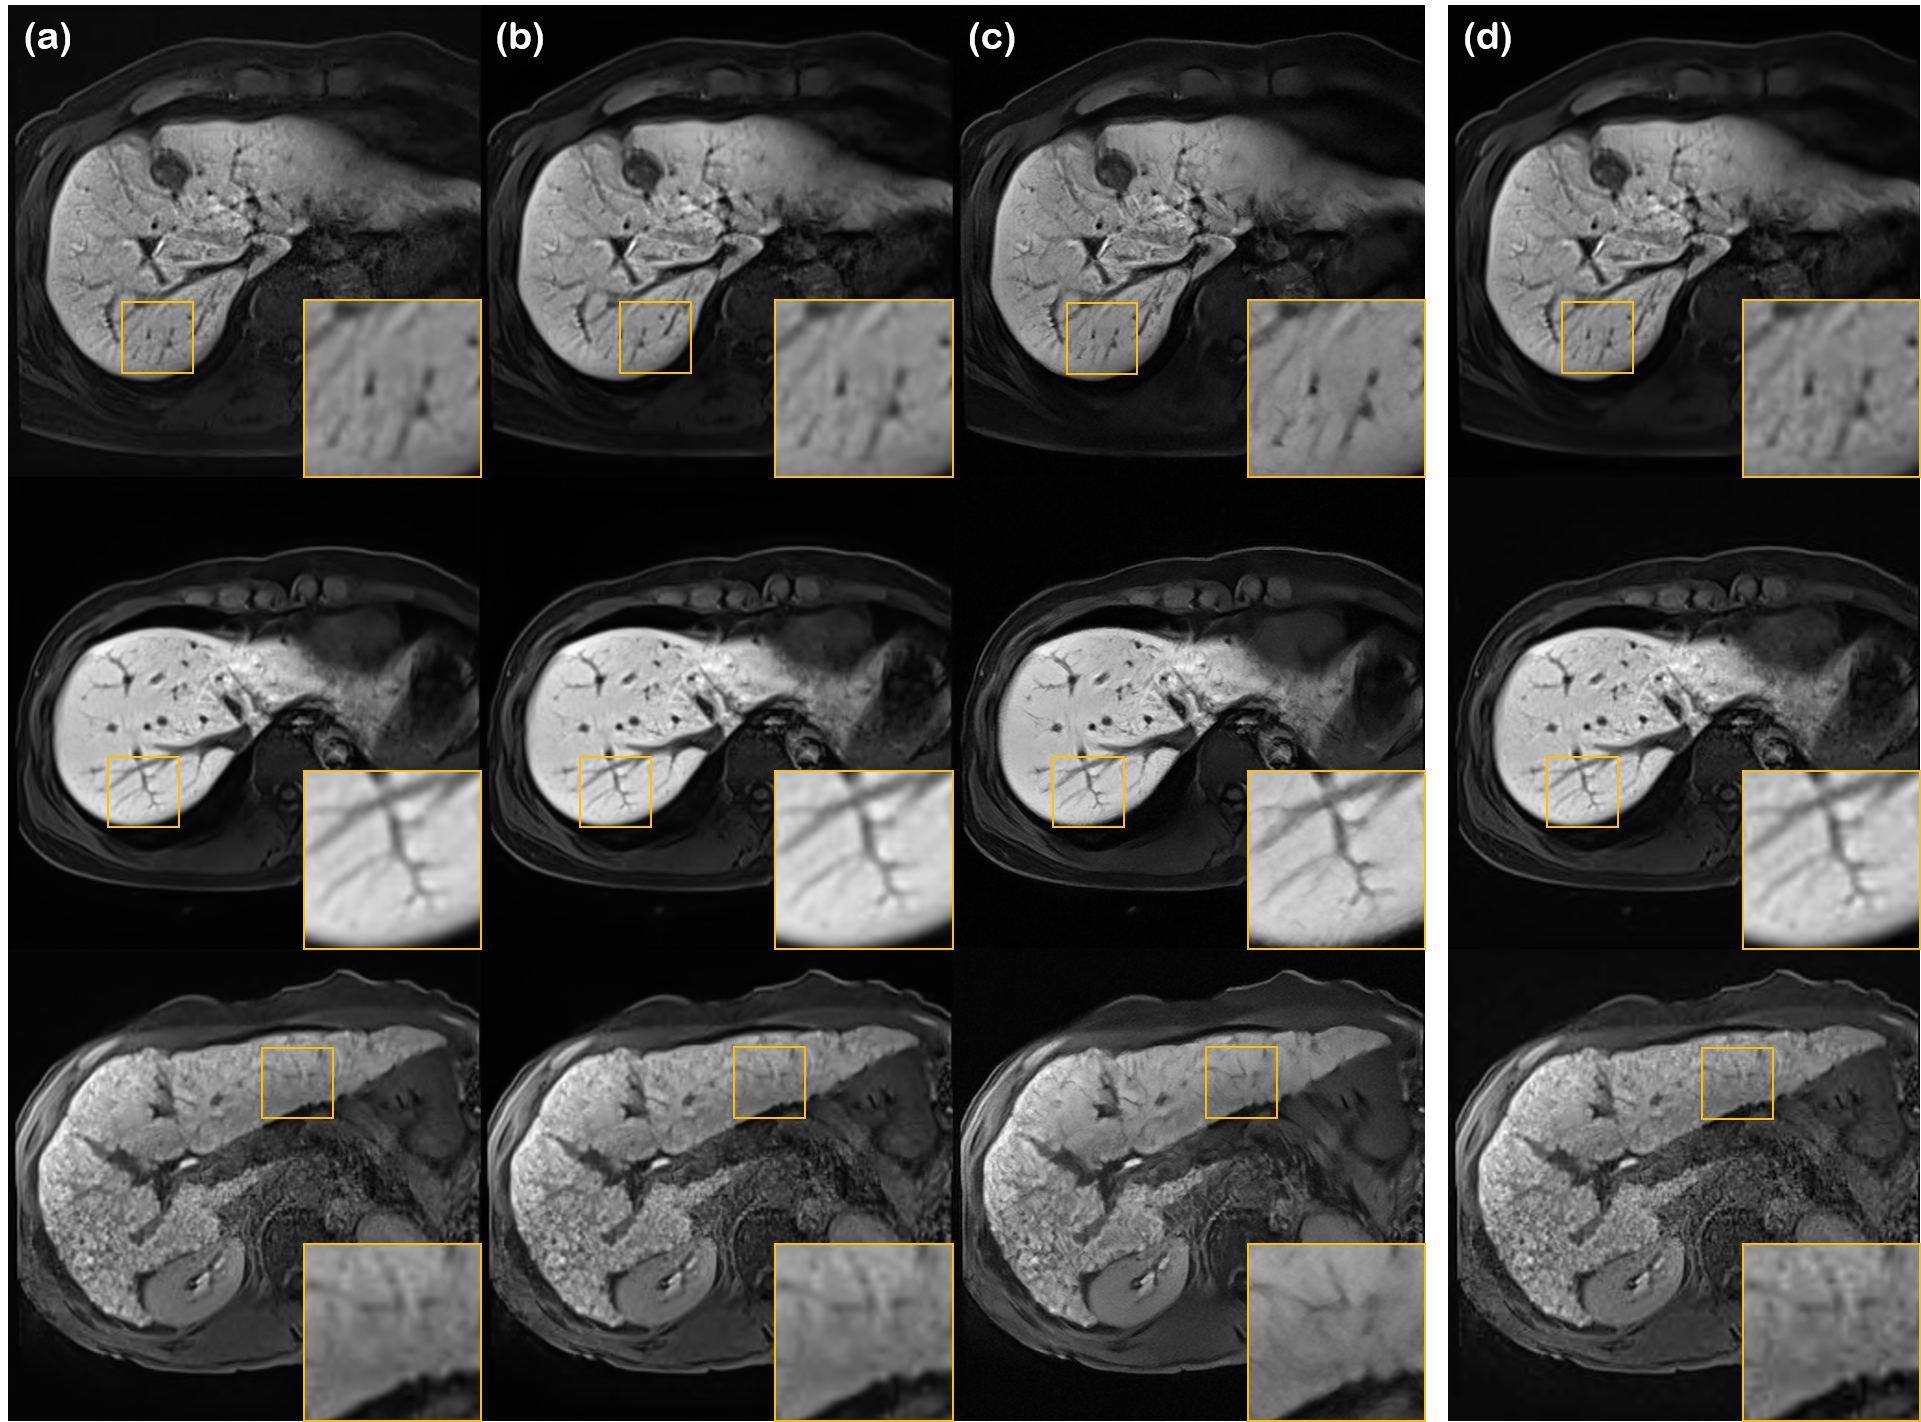

Refer to caption

Figure 6: Ablation study on the post-hoc super-resolution method. (a) Without SR, (b) with SR, and (c) noisy image. White dotted lines indicate the results by the proposed method.

In Fig. 6, we compare the reconstruction results with and without using the post-hoc super-resolution method, with the corresponding metrics reported in TABLE III. From the figure and the table, we see that the additional SR step greatly enhances the resolution, and the CNR, at the expense of a slight decrease in SNR. Hence, we can safely conclude that the proposed method has an overall positive effect on the reconstruction.